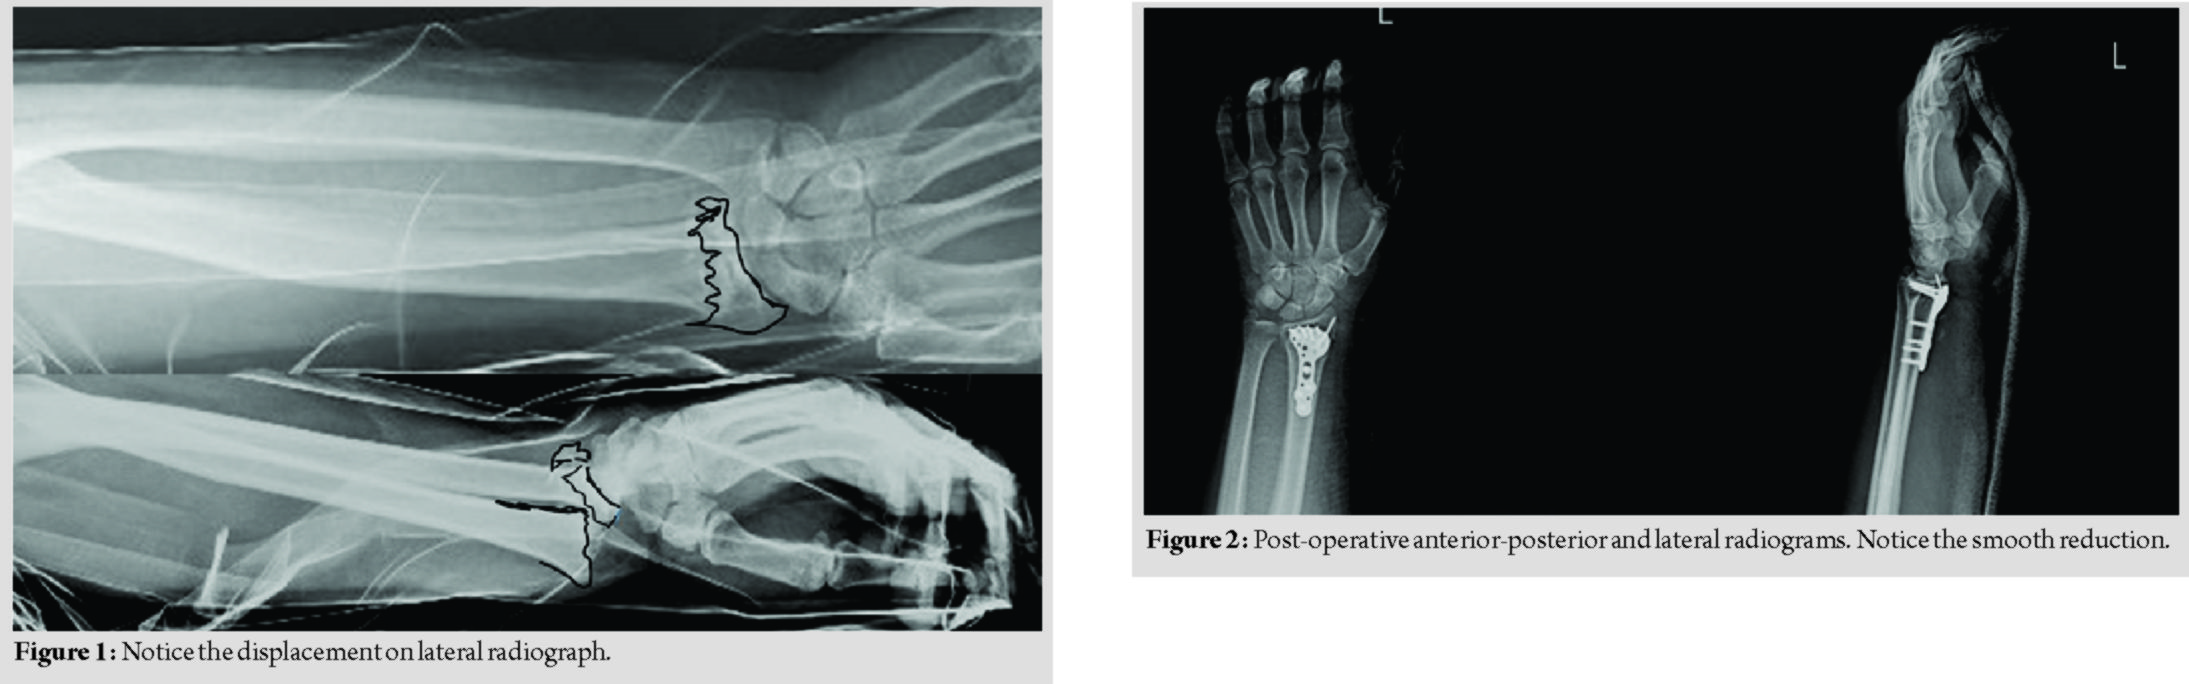

Radiologic examination revealed that the right shoulder was dislocated, and there was a dorsally displaced severely comminuted distal radius fracture in the left wrist with a non-displaced fracture of the ulnar styloid (Fig. 1). The dislocated right shoulder was reduced under sedoanalgesia. The patient was operated electively 1 day after the injury.

Under infraclavicular blockage anesthesia, with a pneumatic tourniquet inflated, approximately 10 cm skin incision was made on the volar aspect of the left wrist. The radial artery was explored and protected. After the fracture was reduced, it was temporarily fixed with 3 K-wires. Then, permanent fixation was achieved using a distal radius volar anatomic plate and screws (Fig. 2).